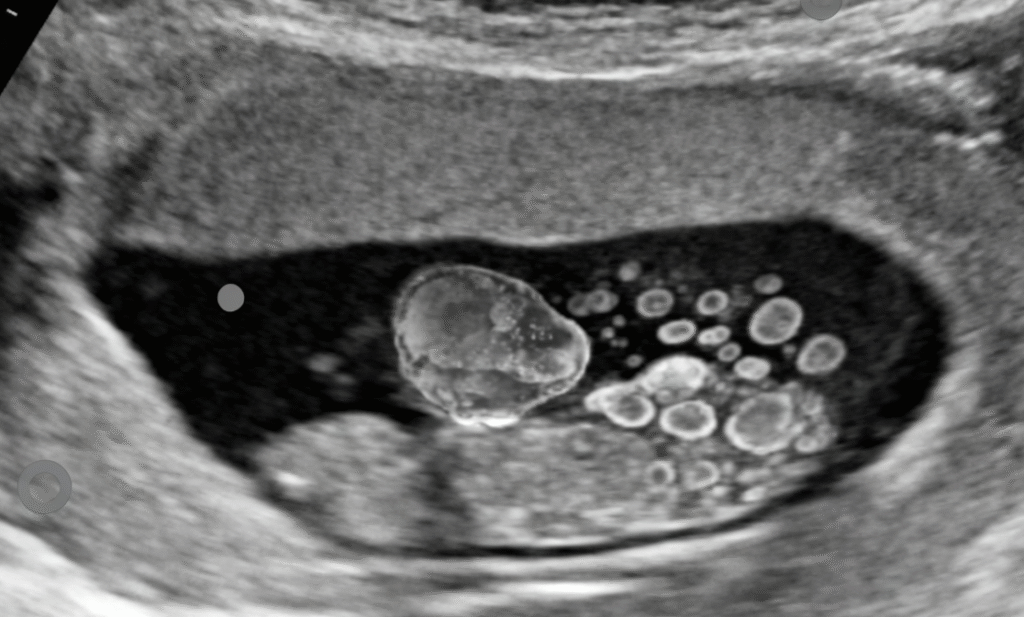

- Imaging:

- Pelvic ultrasound: Solid-cystic ovarian mass, often unilateral